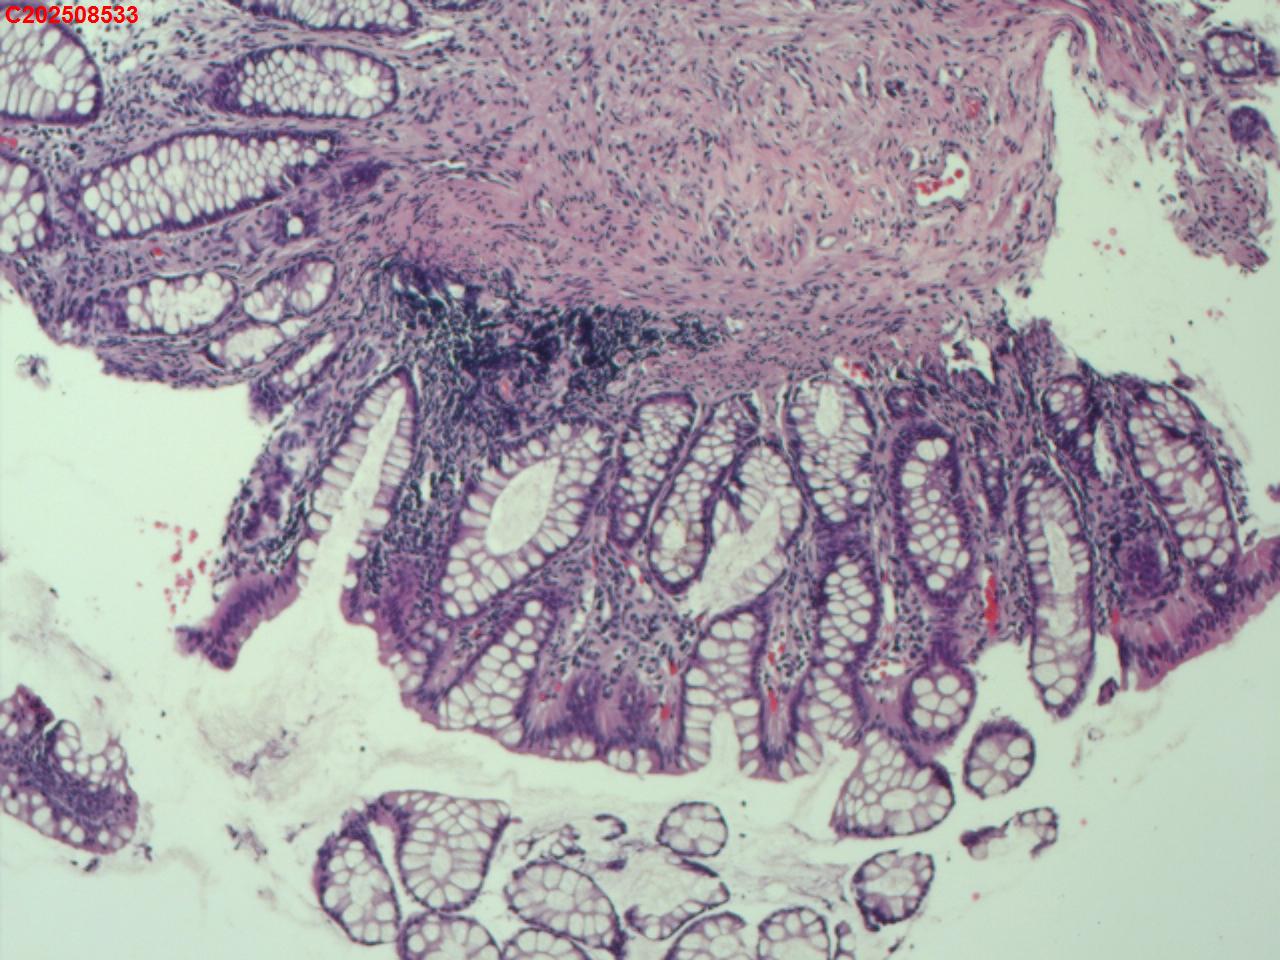

直肠粘膜

性别

男

年龄

48岁

临床诊断

直肠息肉

一般病史

酒精性肝硬化

标本名称

大体所见

直肠可见一枚直径6mm的息肉。

增生性息肉